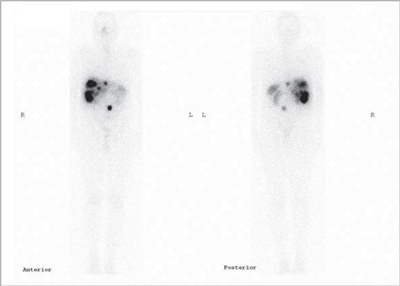

Tumores gastroenteropancreáticos

Este grupo (GEP) constituyen un grupo heterogéneo de tumores neuroendocrinos del estómago, páncreas e intestino. El más frecuente es el tumor carcinoide. El tratamiento primario es la cirugía aún en los pacientes con enfermedad metastásica, debido a que la resección parcial puede mejorar la calidad de vida, sobrevida y estado funcional. Las imágenes cumplen un papel importante para determinar la extensión de la enfermedad al inicio y en el seguimiento. Los estudios realizados con 111In pentatreotide muestran elevada sensibilidad para la detección de GEP a excepción del insulinoma. La sensibilidad para el gastrinoma metastásico, carcinoide y otros GEP son generalmente sobre 80% hasta 94%. La sensibilidad para la enfermedad metastásica tiende a ser superior a la de los tumores primarios (Figura 1) y en muchas ocasiones se encuentran lesiones no detectables por imágenes anatómicas. Utilizando Ga68 análogos de somatostatina se han obtenido excelentes resultados, con sensibilidades entre 82-100% (Figuras 2 y 3). El FDG tiene baja sensibilidad para la detección de estos tumores de lento crecimiento, bien diferenciados y bajo Ki-67, en cambio las imágenes con análogos de somatostatina presentan un patrón opuesto (Figura 4 y 5). Los tumores neuroendocrinos indiferenciados y agresivos presentan marcada avidez por la glucosa y pobre expresión de receptores de somatostatina y viceversa. Se ha visto que los pacientes con tumores con mayor expresión de Ki-67 evolucionan peor que aquellos con bajo Ki-6715. Los tumores neuroendocrinos que captan FDG tienen por lo tanto peor pronóstico16. En un estudio que comparó el rendimiento de cintigrafía con Octreoscan y FDG en pacientes con tumor carcinoide encontró que el 86% de los tumores primarios se localizaban con pentatreotide mientras que sólo el 57% con FDG. Pacientes con metástasis, el 69% fue positivo con el análogo de somatostatina, 47% con FDG y 56% con imágenes anatómicas17. Figuras similares se han obtenido con el uso de PET y Ga68análogos de somatostatina18,19.